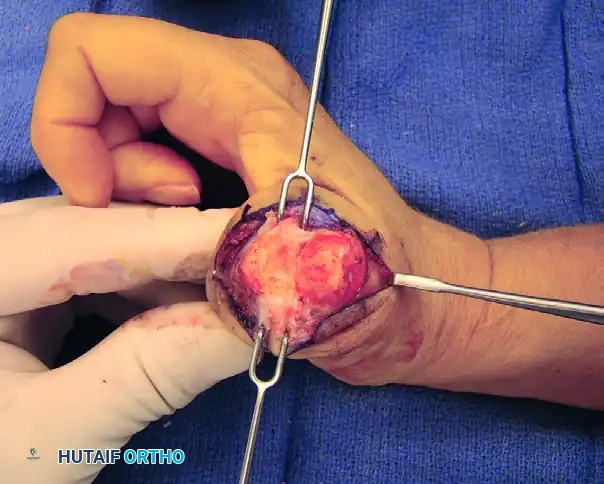

3. Arthrotomy and Joint Debridement

A thorough arthrotomy is required to mobilize the joint and prepare it for fusion.

- Split the dorsal capsule longitudinally to expose the metacarpal head and the base of the proximal phalanx.

- Use a rongeur and sharp dissection to excise all marginal osteophytes, which can tether the joint and prevent adequate positioning.

- Release the radial and ulnar collateral ligaments from their metacarpal origins. This step is crucial for achieving the necessary mobility to dislocate the joint and access the articular surfaces fully.

- Perform a complete synovectomy to remove inflammatory tissue, particularly in rheumatoid patients.

FIGURE 73-40C: Capsule split longitudinally to expose the metacarpal head and proximal phalanx base, followed by excision of osteophytes, collateral ligaments, and synovitic tissue.

4. Joint Surface Preparation

The success of the arthrodesis depends entirely on the quality of the bony preparation. The goal is to achieve broad, flush contact between healthy, bleeding cancellous bone surfaces.

- Technique Options: The surgeon may choose between flat planar cuts (using an oscillating saw) or a cup-and-cone technique (using specialized reamers). The cup-and-cone technique is generally preferred as it preserves thumb length and allows for multi-planar adjustments of the fusion angle prior to fixation.

- Remove all remaining articular cartilage and subchondral bone until punctate bleeding from the cancellous bone is observed.

- Optimal Fusion Position: The joint should be provisionally reduced and held in the ideal position for arthrodesis:

- 10 to 15 degrees of flexion

- 10 to 15 degrees of pronation (to allow the thumb pulp to face the index finger)

- 0 to 5 degrees of abduction

FIGURE 73-40D: Exposure of subchondral bone to obtain full contact of the raw cancellous metacarpal and proximal phalangeal surfaces.